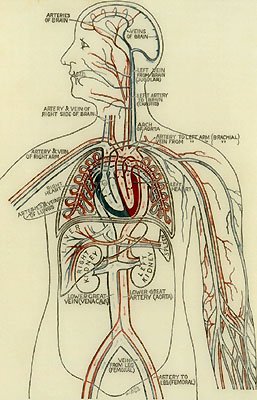

facing 110 Diagram of the Circulatory System

116 The Exterior of the Heart

117 Diagram of Valves in the Veins and Heart

118 The Blood-Route trought the Heart